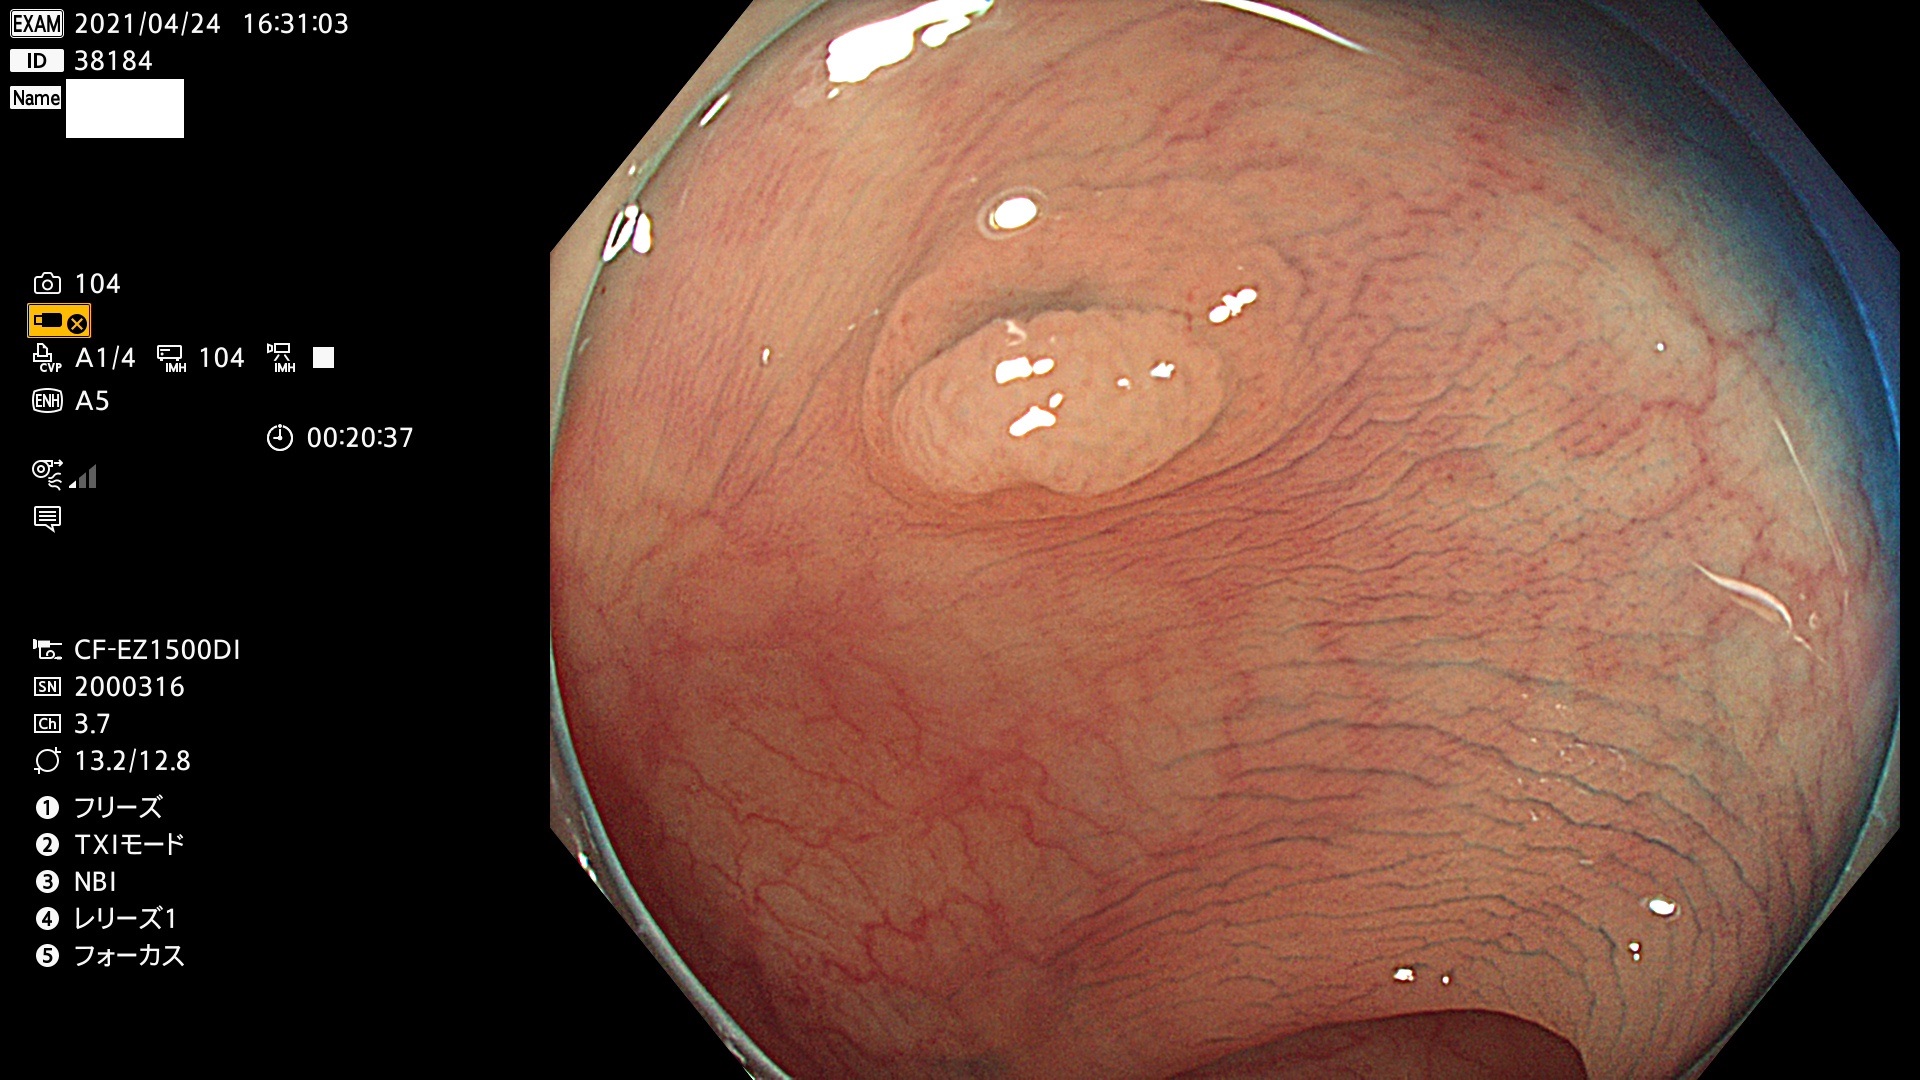

発見困難で危険性の高い平坦型病変(上記100名より抽出) ![]()